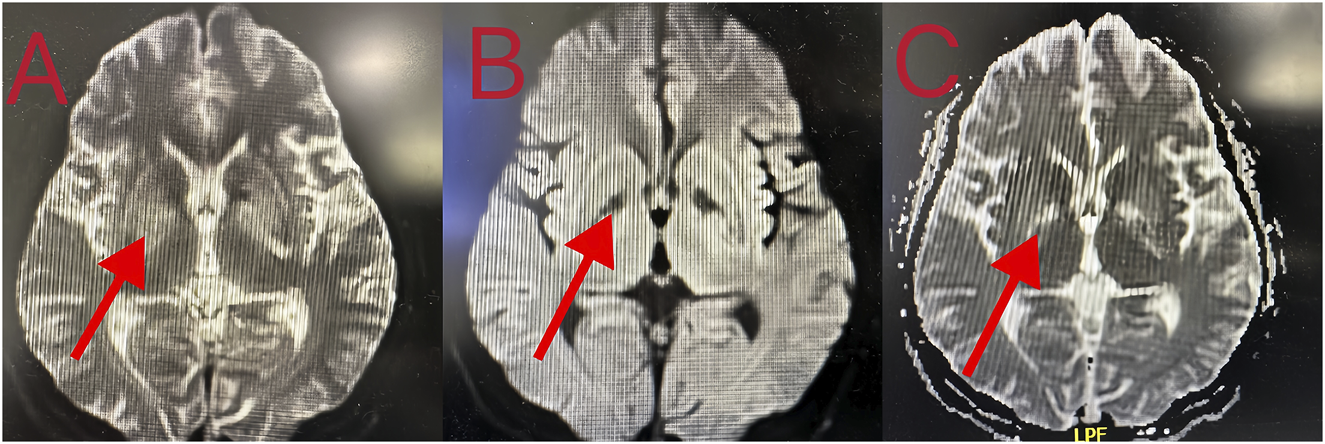

Patient 8 was a 53-year-old man who ingested 10 g of compound schizonepeta fumigation lotion on 4 February 2024, and was admitted to a local hospital. An electrocardiogram conducted at the local hospital revealed ventricular tachycardia and premature ventricular contractions (Figure 2D). After admission, he continued to experience malignant arrhythmias and unstable circulation. He received extracorporeal membrane oxygenation supportive treatment for 4 days, tracheal intubation and assisted ventilation for 8 days, hemofiltration five times, and hemoperfusion five times. For further diagnosis and treatment, he was transferred to our hospital on 16 February 2024. Physical examination on admission (at our hospital) revealed a body temperature of 38.5°C, heart rate of 92 beats/min, respiration rate of 16 breaths/min, blood pressure of 135/82 mmHg, an impaired mental state, and an inability to communicate. The electrocardiogram upon admission revealed a sinus rhythm and non-specific T-wave abnormalities. Laboratory test results were as follows: white blood cell count, 16.50 × 109/L (3.5–9.5 × 109/L); neutrophil ratio, 77.50% (40%–75%); alanine aminotransferase, 61 IU/L (9–50 U/L); creatine kinase, 649 IU/L (55–170 IU/L); and creatine kinase isoenzyme, 4.30 ng/mL (0.3–4 ng/mL). At the local hospital, measurement of aconitine, hypoaconitine, and mesoaconitine concentrations revealed blood levels of 205, 58, and 23 ng/mL, respectively. However, upon transfer to our hospital, these compounds were untraceable in the patient’s blood. The admission diagnosis was aconitine poisoning. The patient underwent electrocardiographic monitoring, organ protection, anti-infective treatment, fluid replacement, nutritional support, and other comprehensive treatments. On day 3 of admission, his white blood cell count was 22.50 × 109/L (3.5–9.5 × 109/L), neutrophil ratio was 87% (40%–75%), creatine kinase level was 182 IU/L (55–170 IU/L), and liver and kidney functions were normal. Chest computed tomography revealed slight inflammation in both lungs and a partial left rib fracture (Figures 3A, B). Brain magnetic resonance imaging revealed symmetrical abnormal signals in bilateral basal ganglia and bilateral parietal and temporal cortices, which was considered to be due to toxic encephalopathy based on his medical history (Figures 4A–C). Salvianolate (200 mg qd) was given to improve microcirculation symptomatic treatment. On day 7 of admission, white blood cell count, 12.98 × 109/L (3.5–9.5 × 109/L), the liver and kidney functions and myocardial enzymes were normal. After 18 days of treatment, the patient improved and was discharged. The patient was discharged for local rehabilitation. During the recent telephonic follow-up, the patient basically returned to normal but still had stuttering and a low voice tone. The family members will bring the patient to the hospital for reexamination in the near future.

Figure 4. (A–C) Brain MRI showing that the density of nuclei in the bilateral basal ganglia was generally reduced, which was consistent with toxic encephalopathy.